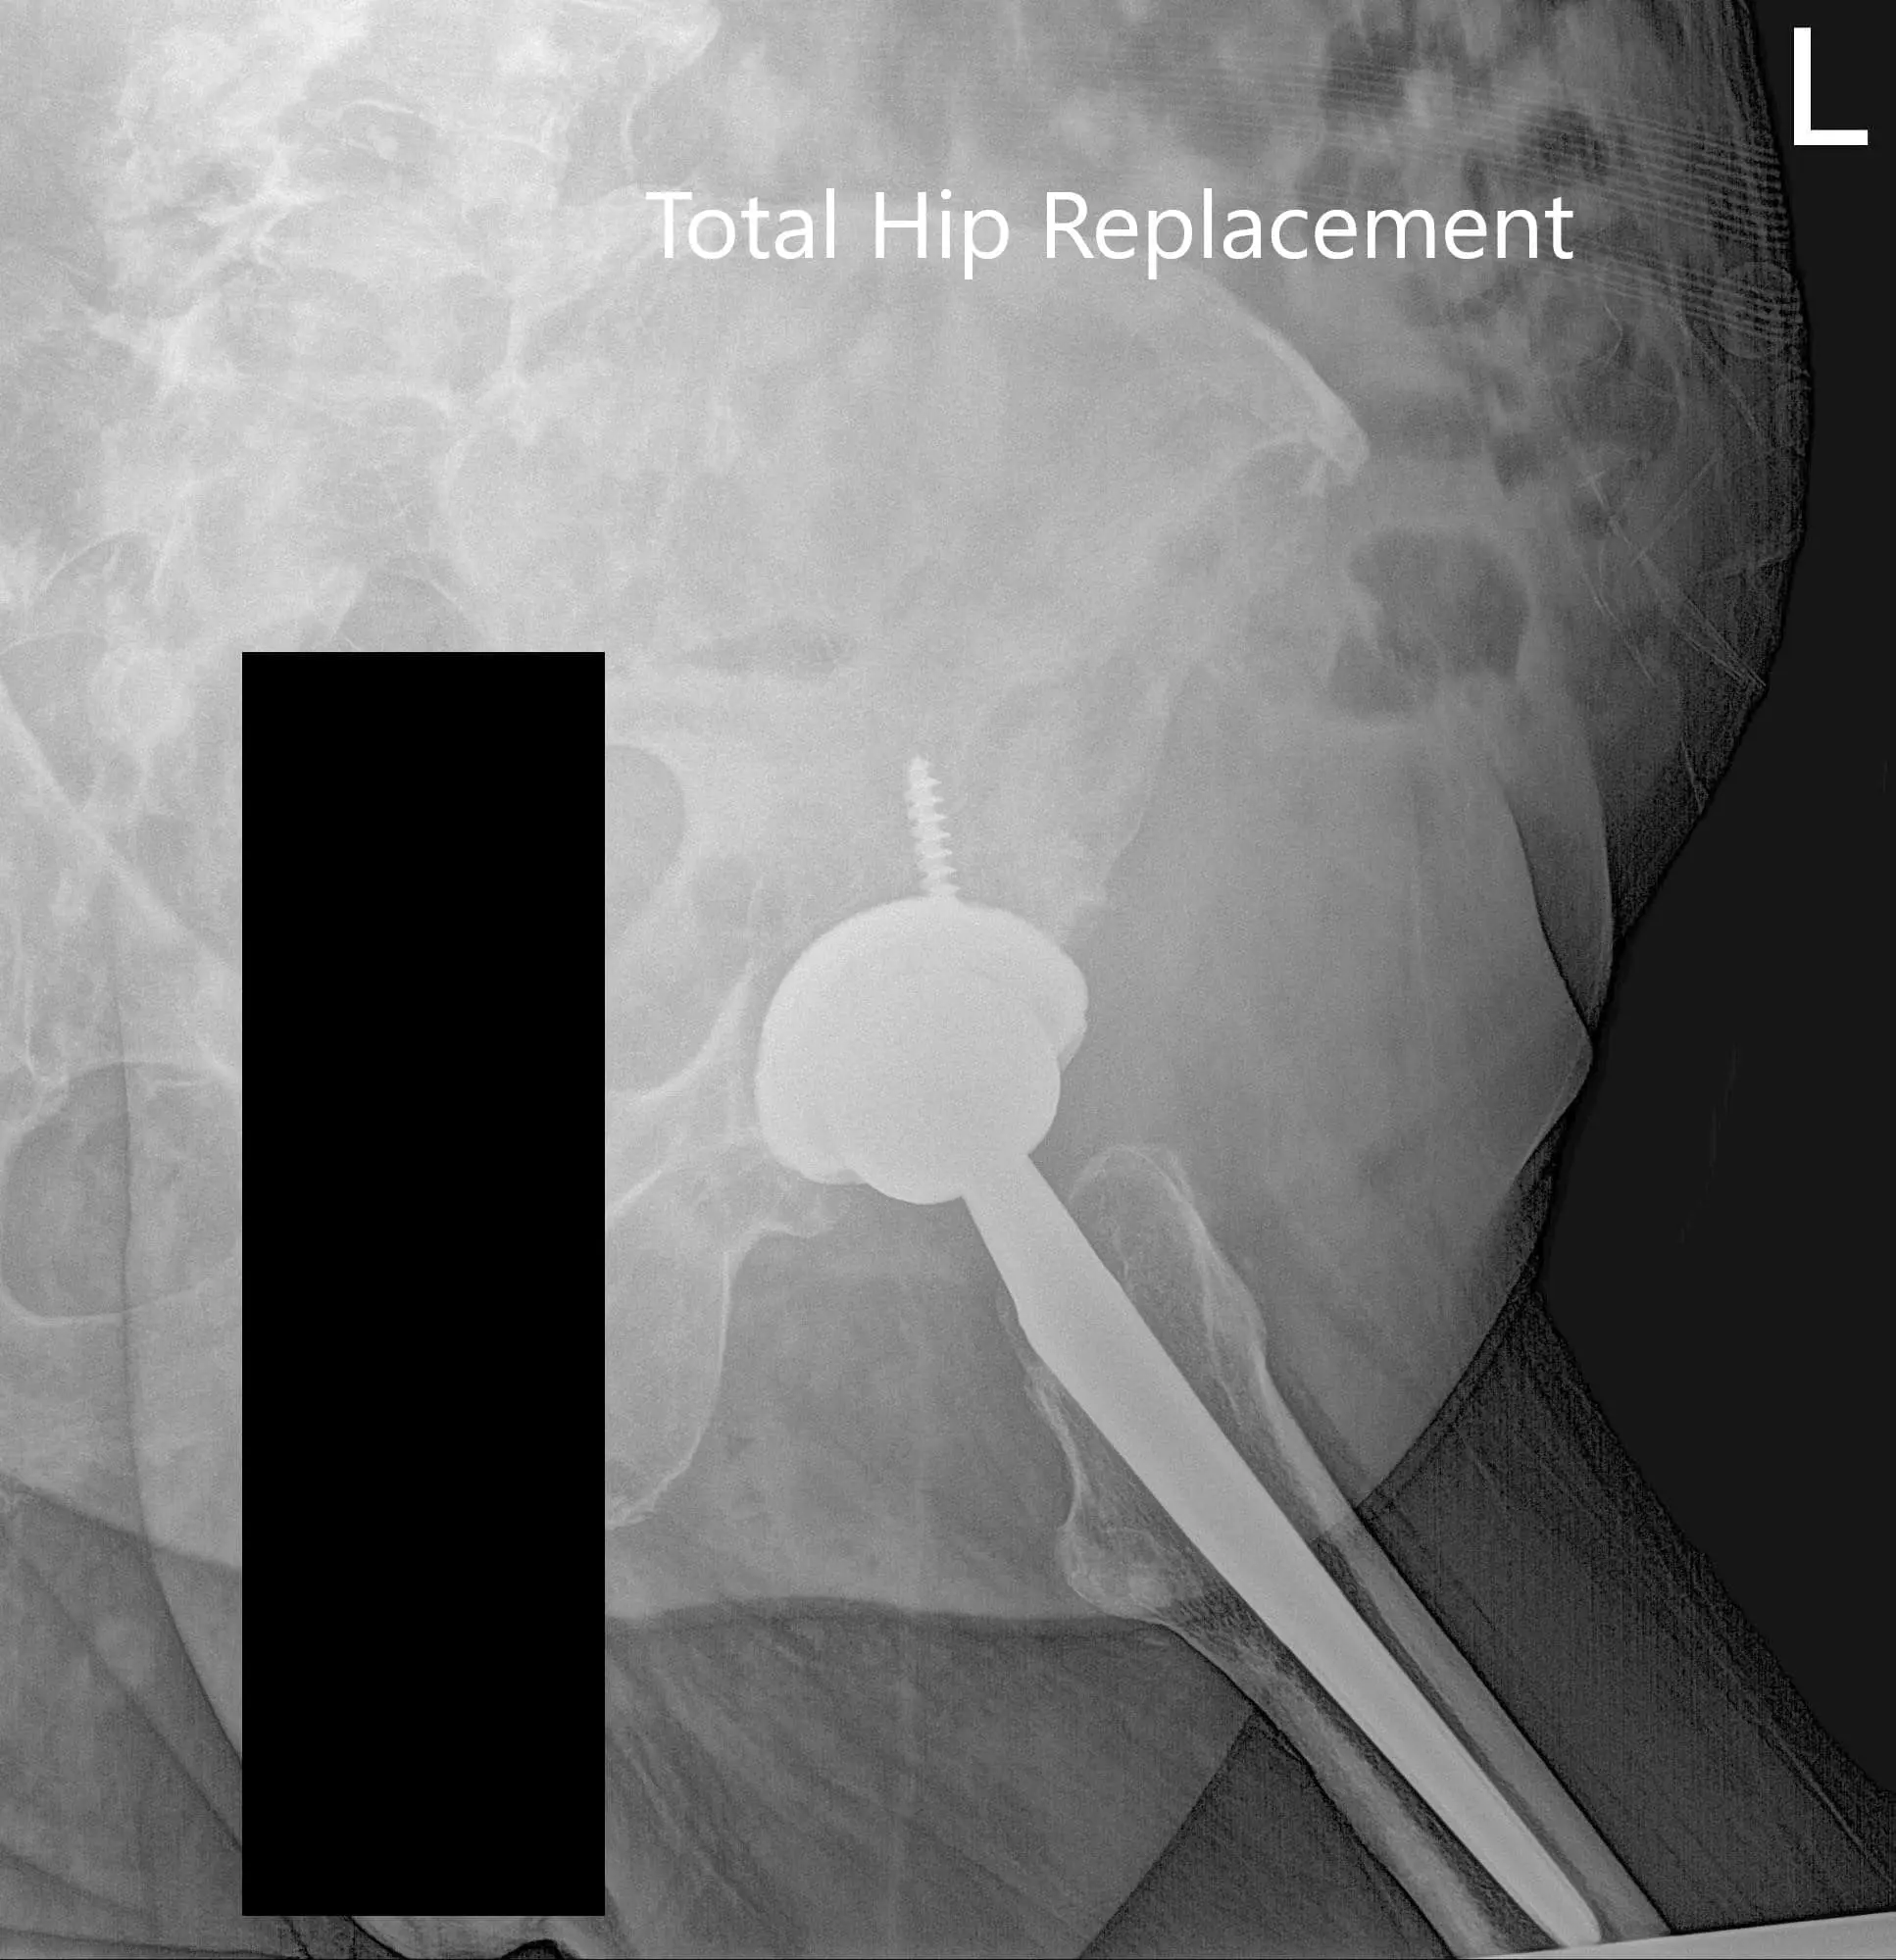

Postoperative X-ray of the Pelvis and lateral view of the left hip

Postoperative X-ray of the Pelvis and lateral view of the left hip - img 2

Postoperative X-ray of the Pelvis and lateral view of the left hip.

IMPLANT USED: Acetabulum shell 54-mm with 0-degree polyethylene insert, 36-mm inner diameter with a femoral head, 36 mm plus 5 with a 6.5 mm x 30 mm screw.